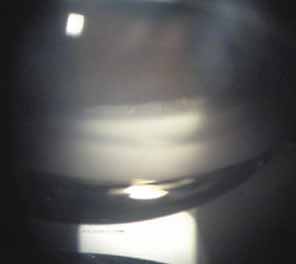

Over the past two decades silicone oil (dimethylpolysiloxane) has enjoyed a resurgence in the repair of complicated retinal detachments. In 1967, Watzke36 found no pressure elevation attributable to silicone but described droplets in the superior angle that result from silicone's lower specific gravity (buoyancy) compared with water. Silicone-induced glaucoma does occur, however, and one possible mechanism is an acute pupillary block due to the buoyancy of the silicone sometimes combined with overfilling the aphakic eye (Fig. 5). This can be averted by performing an inferior iridectomy and by paying careful attention to the silicone volume injected. A second mechanism involves chronic obstruction of an open angle by emulsified silicone microbubbles (more likely with low viscosity silicone, 1,000 centistokes, than high viscosity silicone, 12,500 centistokes) (Fig. 6), pigmented cells, and silicone-laden macrophages or silicone-induced fibrosis of the trabecular meshwork due to possible inherent fibrogenicity of this compound.37,38 Treatment of this open-angle glaucoma is generally medical, although silicone removal may be required. Although some studies have confirmed the presence of emulsified oil in the anterior chamber as a strong predictor of pressure elevation, others do not, suggesting that multiple factors are at play.39,40,41,42 Often this can only be seen on gonioscopy, and removal of the oil, if possible, is beneficial in some cases. Sometimes an expected pressure elevation that would otherwise occur may be muted by concomitant cyclitic membrane formation or hypotony associated with recurrent retinal detachment. The use of shunt procedures in this difficult glaucoma has led to the unusual complication of silicone oil escape into the subconjunctival space43,44 (Fig. 7). Whether placed superiorly or inferiorly, shunts should probably be avoided in these eyes unless the silicone oil can first be safely removed. Transscleral diode laser cyclophotocoagulation has been proven to be an excellent noninvasive option in treating these eyes for recalcitrant pressure elevation.45,46